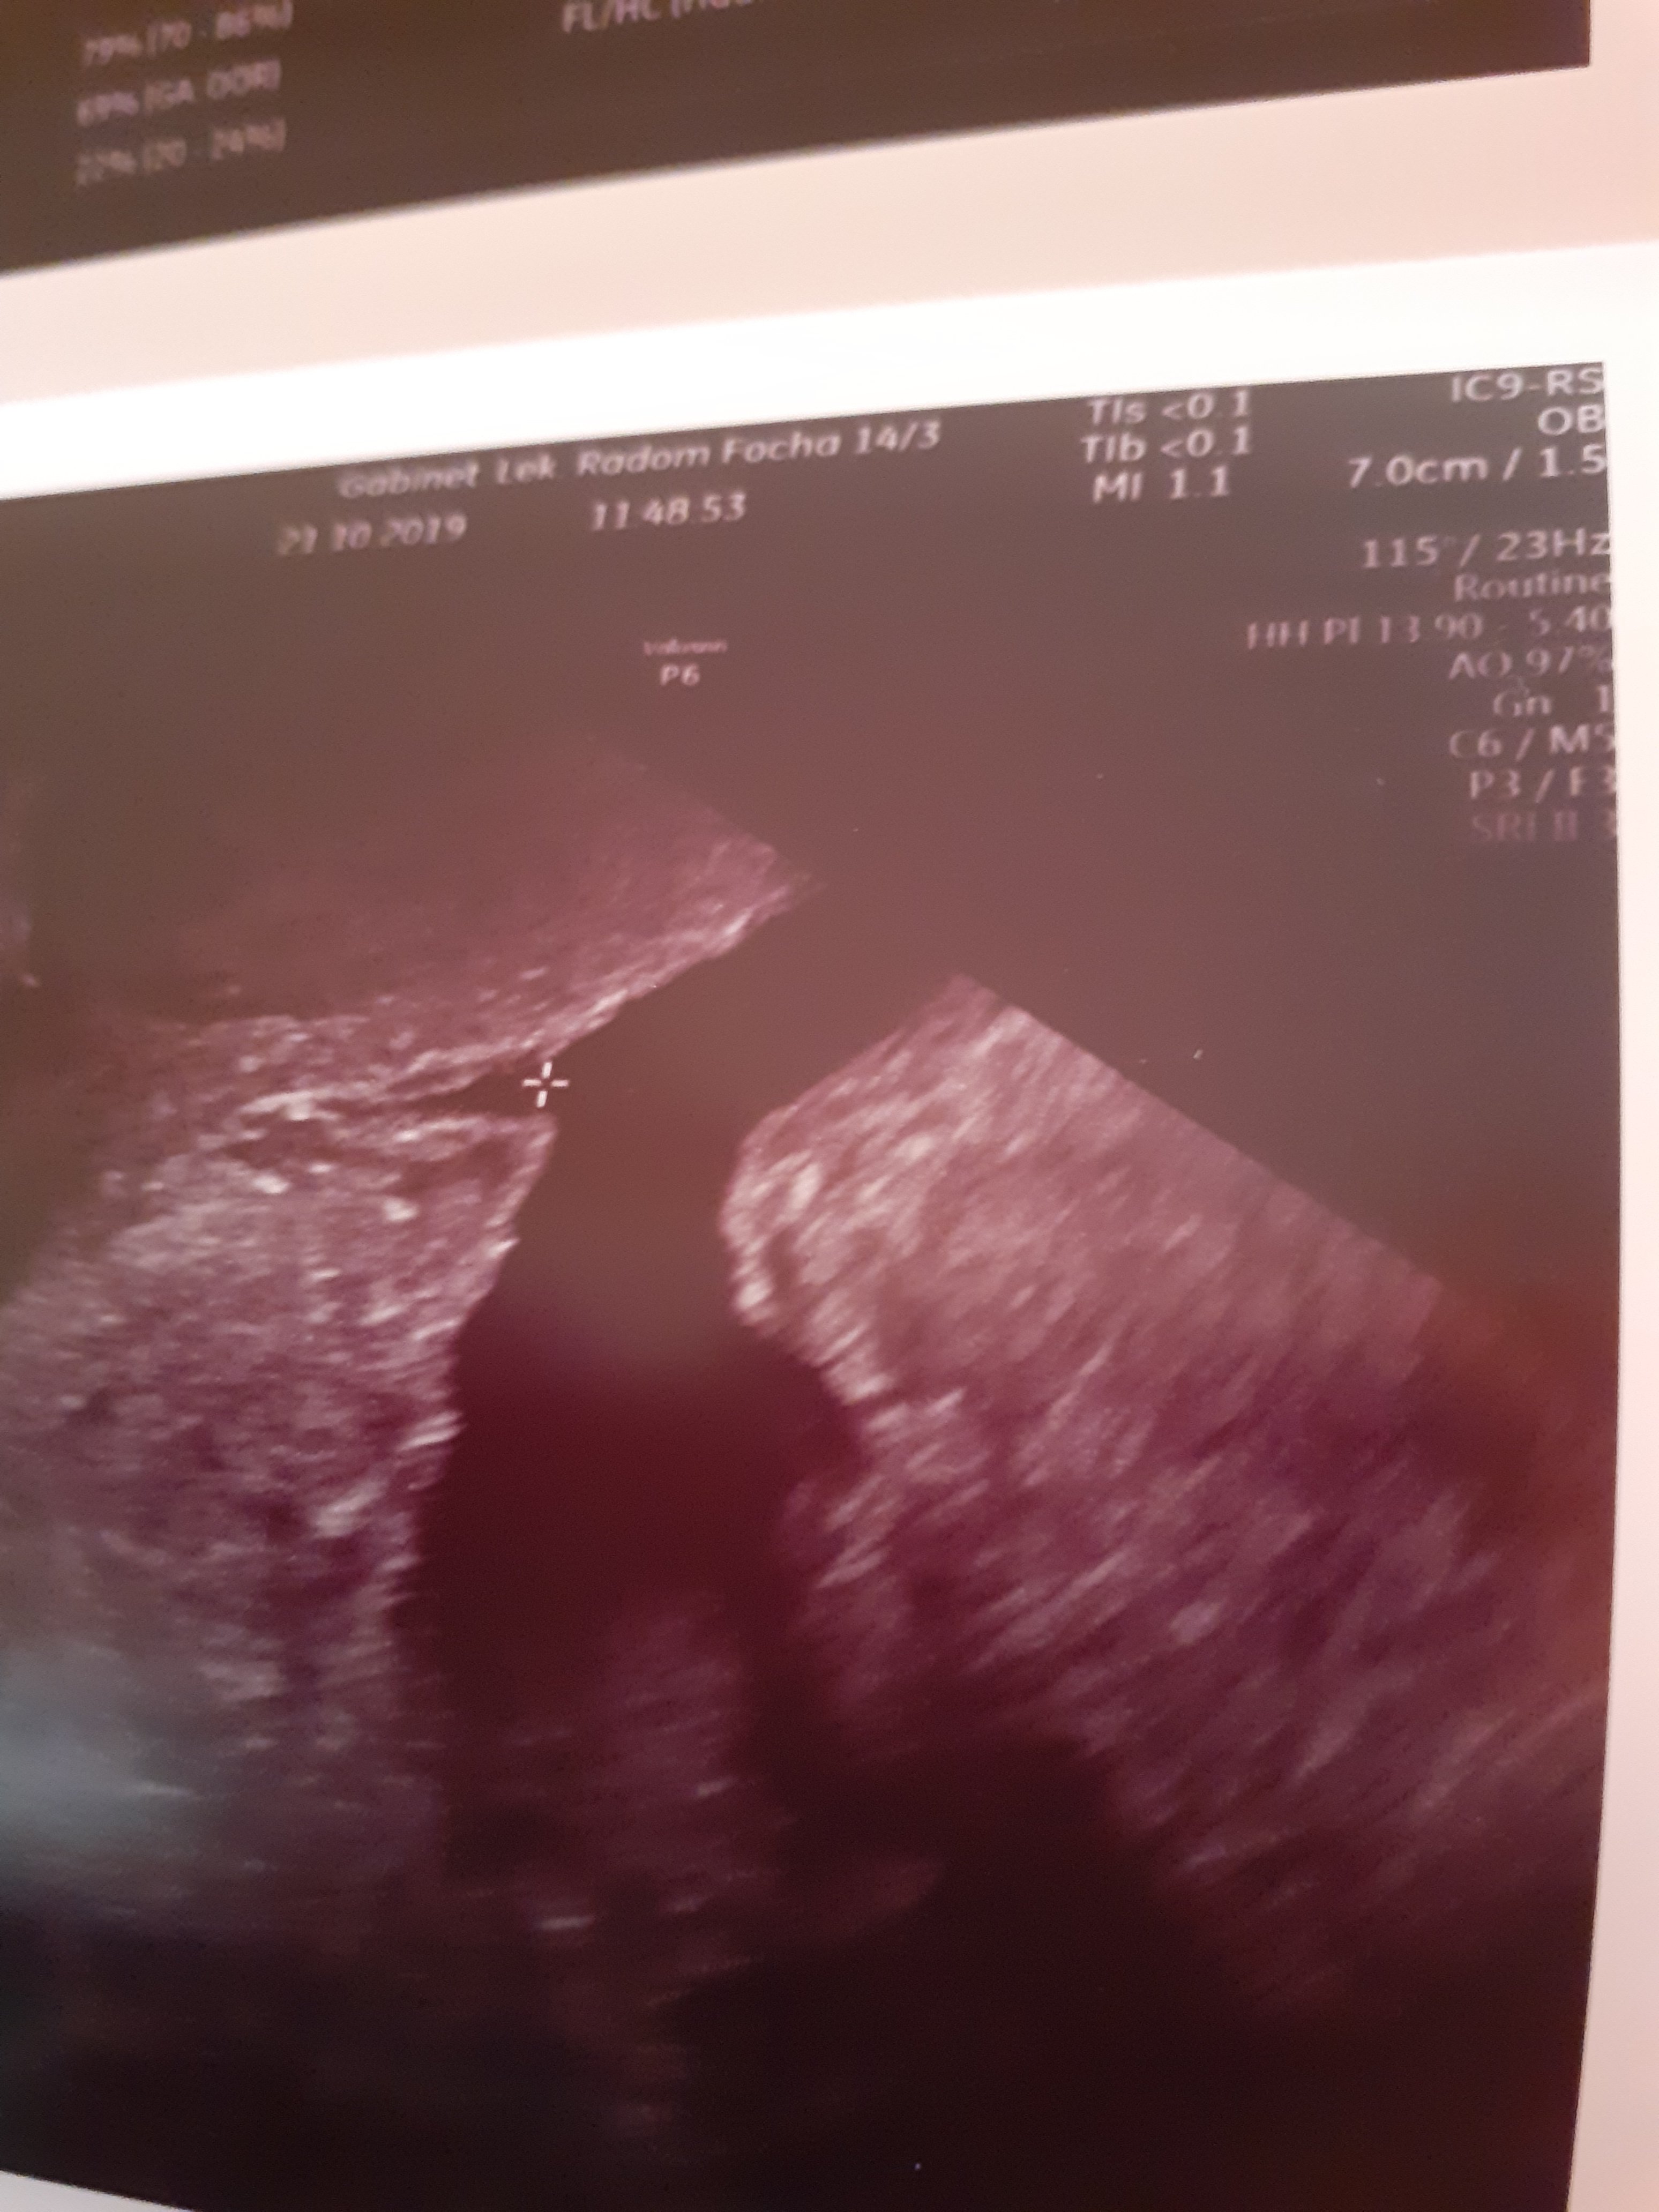

to moje zdjęcie przezpochwowe szyjki i wydaje mi się że Cię trochę od środka otworzyła czy tak musi bycW pierwszej ciazy już w 12tyg miałam 26mm

to moje zdjęcie przezpochwowe szyjki i wydaje mi się że Cię trochę od środka otworzyła czy tak musi byc